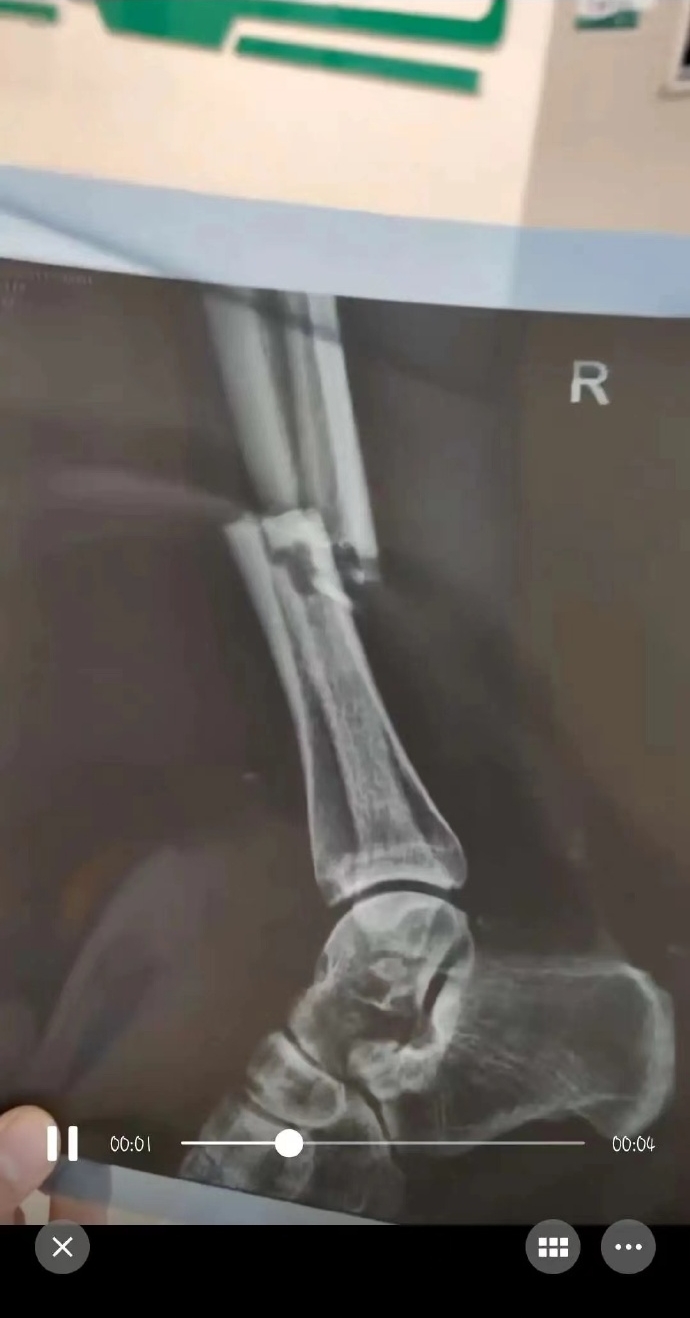

据网传视频显示,广州队前锋帕尔曼江在参加新疆传统足球赛事阿图什杯时遭遇“断腿”重伤,赛后拍片帕尔曼江小腿骨折。

注:以上图片均为网传,各位吧友还需等待官方伤情公告或辟谣